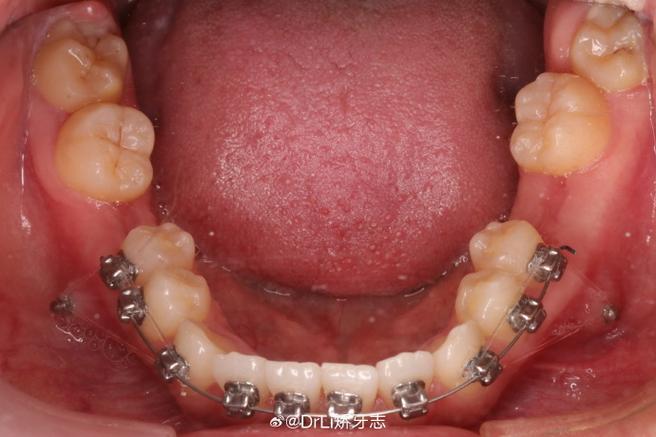

正畸弓丝末端脱出是牙齿矫正过程中较为常见的并发症,指固定在牙齿托槽上的弓丝末端从末端管(最后一颗大牙后方的金属管)中滑出,可能刺伤口腔软组织或影响矫正效果,了解其发生原因、处理方法及预防措施,对保障矫正进程顺利至关重要。

| 弓丝材质特性 | 镍钛弓丝具有超弹性,若初始弓丝选择过粗或牙弓形态与弓丝不匹配,弓丝在口腔内温度变化下可能发生“回弹”,导致末端超出末端管范围。 | 牙弓不对称、牙齿严重扭转的患者,或矫正初期更换较粗弓丝时。 |